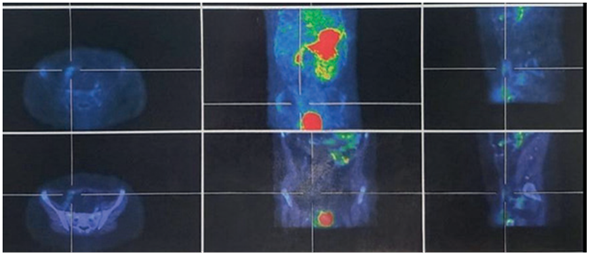

Se realizó fibrogastroscopía que no identificó lesiones en la mucosa gástrica y esofágica. El centellograma con tecnecio-99m evidenció la presencia de mucosa gástrica heterotópica en fosa ilíaca derecha compatible con DM (Figuras 1 y 2).

Figura 1 Gammagrafía con Tc99m-pertecnetato: hiperactividad focal en fosa ilíaca derecha.

Figura 2 Mucosa gástrica ectópica positiva.

Cuando se presenta con sangrado, el método de diagnóstico más preciso es la gammagrafía con tecnecio-99, dicho radiofármaco tiene una alta afinidad por la mucosa gástrica, y, tras su aplicación intravenosa, se realiza una centellografía para identificar la localización de mucosa ectópica. Se trata de un estudio no invasivo, no requiere de anestesia, presenta una sensibilidad de 85% a 90% y una especificidad de 97%. El refuerzo de la captación farmacológica con pentagastrina o antihistamínicos H2 puede mejorar la precisión del estudio1,5,8-11,16-18,22.